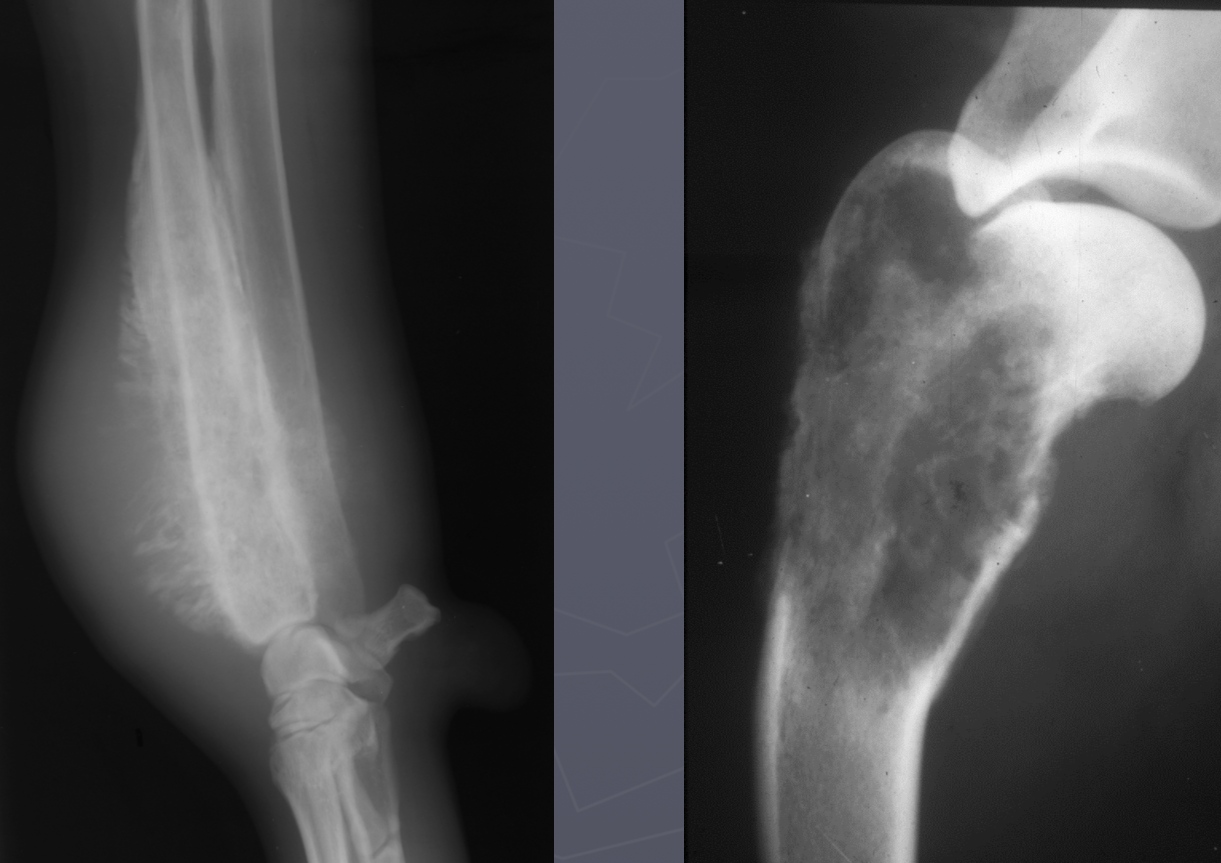

primary bone tumor signalment

large/giant dogs

bimodal age distribution

males

lung mets

monostotic - no cross joint

OSA - away from elbow, towards knee, distal tibia

AGG lesion

primary bone tumor